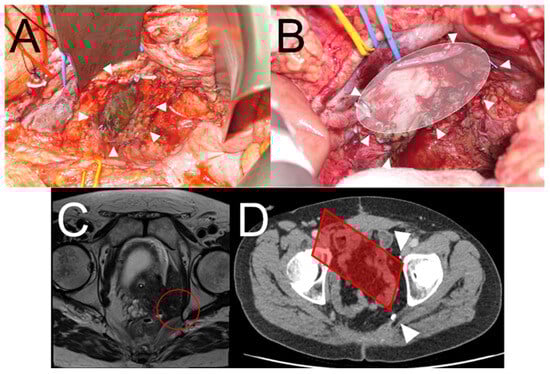

The key goal of IOERT is to avoid re-recurrence in margin-concerning cancers by mitigating for a possible microscopic R1 resection through the use of a radiotherapy boost directed at residual clones. Consequently, the most important primary outcome measure of IOERT efficacy for any future late-phase study is IOERT field local control. However, at the time of this study’s design, there was no optimal method for accurately charting the intraoperative IOERT field for future surveillance, and IOERT field evaluation was poorly reported [25]. As a result, a method of marking out the IOERT field by applying radiopaque surgical clips to the margin of the IOERT field with the applicator still in situ (Figure 2) was devised. This simple but novel technique allows for precise tracking of the IOERT field postoperatively in sequential scans to report any evidence of IOERT field local recurrence or out-of-field local recurrence.

(A) View of the pelvic sidewall following pelvic exenteration and resection of pelvic sidewall including internal iliac vessels. The arrowheads show the application of metallic clips to the IOERT field for future tracking. (B) Similar view following pelvic exenteration with en bloc resection of the pelvic sidewall vessels exposing the sciatic nerve. The arrowheads and schematic oval shape show the site of the IOERT field. (C) Preoperative MRI of patient needing pelvic exenteration who was potentially eligible for the ELECTRA trial. The red circle shows the area at greatest risk of an R1 surgical resection. (D) Same patient in (C) postoperatively who received IOERT. The arrowheads show the ability to track the IOERT field with diagrammatic representation of the IOERT applicator as it would have been placed per-operatively.